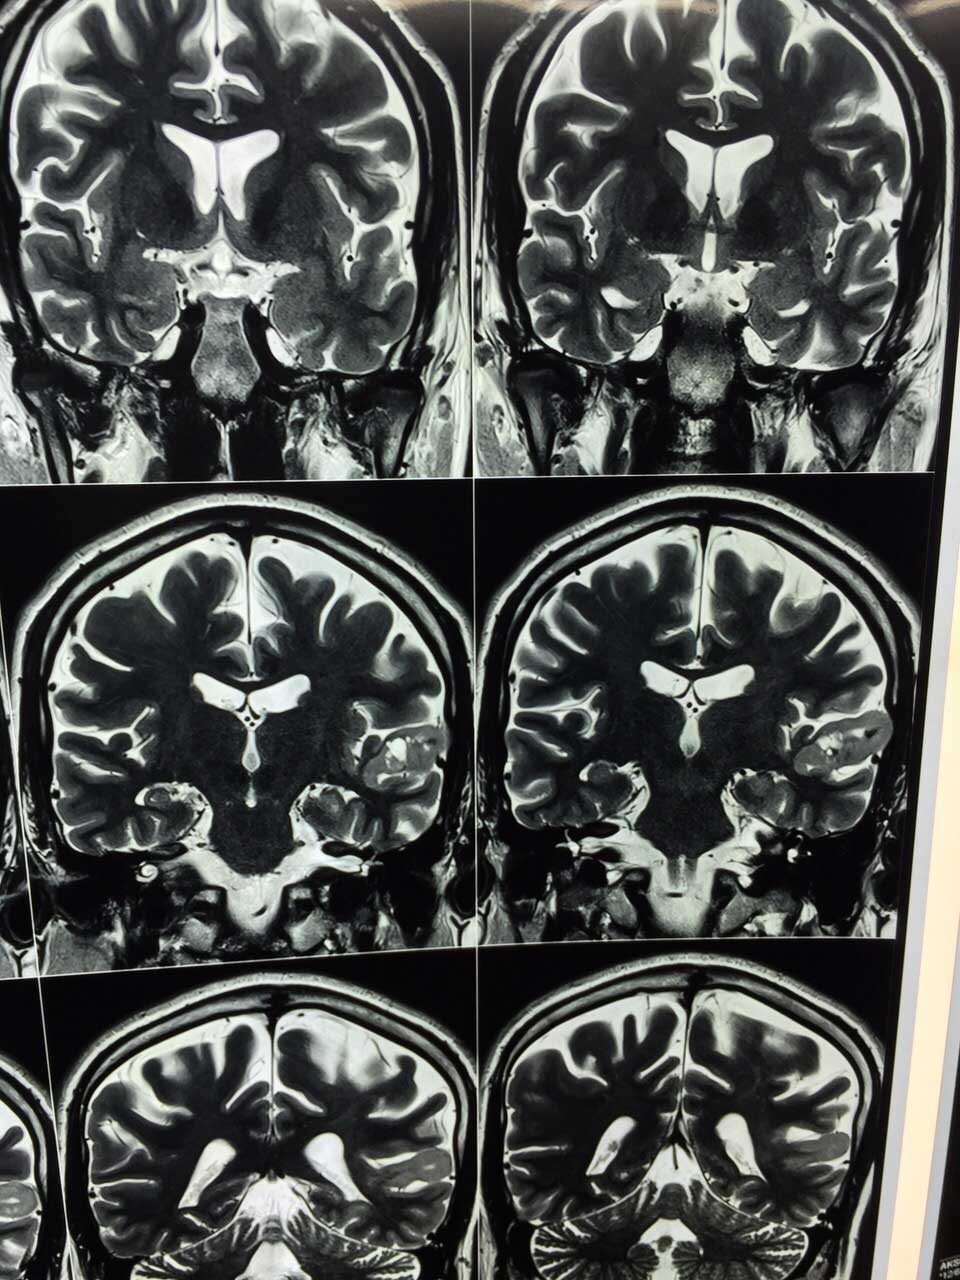

Cavernoma Pre Op Mri